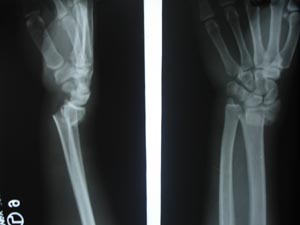

Fall on outstretched hand resulting into fracture neck of radius with displacement. Obtain two views as nearly as possible at right angles to each other. Here there is obvious displacement or break in the thick cortex.